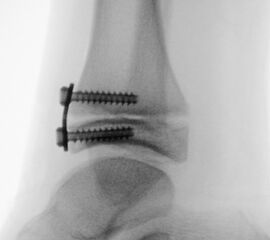

Knick-Senk-Platt-Fuß Korrektur mit dem Canalis Tarsi Spacer

In der Korrektur des schmerzhaften, aber flexiblen Knick-Senk-Fußes oder Plattfußes ist die Schraubenarthrorise mit einem Sinus tarsi oder besser bezeichnet als Canalis tarsi Spacer und alternativ mit einer Calcaneus-Stopp-Schraube seit vielen Jahren ein etabliertes Verfahren und führt zu einer kompletten Korrektur von flexiblen Knick- und Plattfuß-Fehlstellungen (Abb. 7). Die nötige Schnittlänge über dem Sinus tarsi beträgt für beide Verfahren 1 cm.

Abb. 7 a-e: Knick-Senk-Fuß prä- und postoperative Situation (a-b), ventrale und dorsale Ansicht (c-d). Laterale Ansicht des Hautschnittes über dem Sinus tarsi (e).

Zum Lesen der Bildbeschreibung und zur Vollansicht bitte die Bilder anklicken. Bilder: A. Helmers.